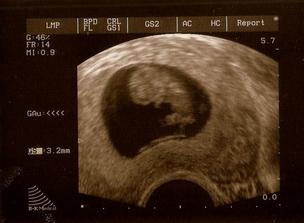

♥ 1. kontrola 4/4 (7+2tt), srdíčko bije

♥ kontrola proběhla v pořádku, doktor nás vrátil na 8+6 tt (podle prvního UZ to mělo být už 10+0), prcek má asi 3,2 cm a dostali jsme průkazku 🙂)